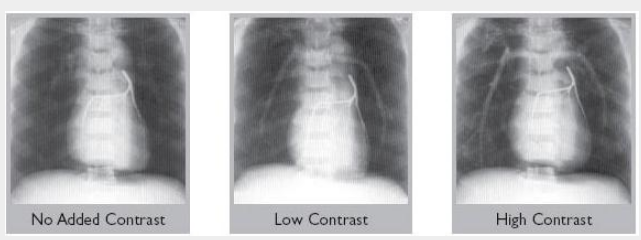

All models are available with blood-equivalent pulmonary arteries, or with low or high contrast media added.

Different Degrees of Vascular Contrast Available